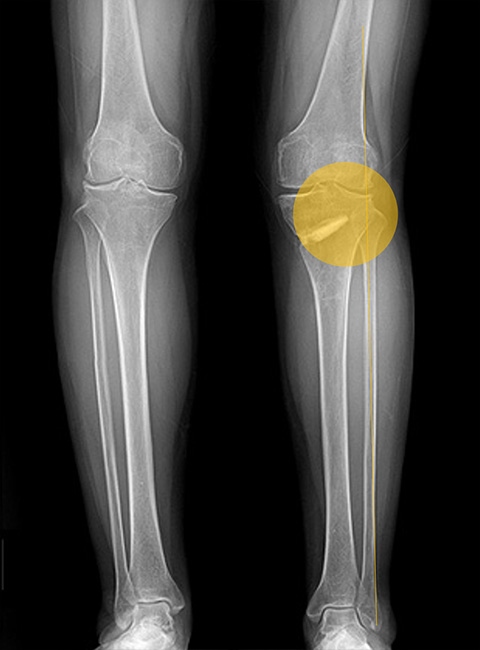

Before

무릎 안쪽 연골 간격이 좁아져 통증을 유발하는 상태

-

After

하중을 무릎 바깥쪽으로 분산시켜 좁아져 있던 무릎 안쪽 간격이 넓어짐 (금속판 제거 후 삽입한 인공뼈도 완전히 유합된 상태)